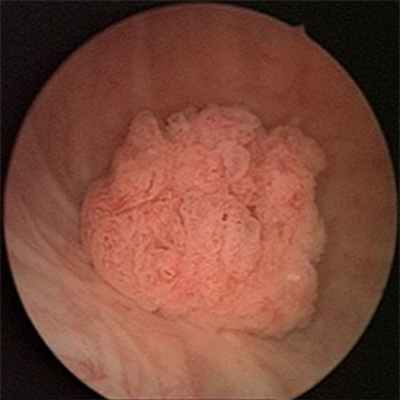

Ведущим методом диагностики рака мочевого пузыря является цистоскопия. Метод заключается в осмотре полости мочевого пузыря. При цистоскопии можно оценить состояние слизистой мочевого пузыря, размеры, количество, локализацию, внешний вид, распространенность опухоли, а также вовлеченность устьев мочеточников.

Морфология злокачественных образований такова: свыше 90% выпадает на долю переходно-клеточных опухолей; до 5% - плоскоклеточные; аденокарцинома и саркома - до 2%; 1% - папиллома. Самый редкий рак мочевого пузыря - мелкоклеточная и веретеноклеточная карцинома.

И также опухоль подразделяется на папиллярный, инфильтративный, плоский, узелковый, внутриэпителиальный характеры роста. Возможно комбинированное развитие новообразования - рак одновременно имеет несколько признаков.

- Эндоскопия позволяет визуально обнаружить внешний вид неоплазии, её размер и локацию. К тому же это обследование даёт возможность взять биопсию и осуществить морфологическое подтверждение рака мочевого пузыря.

На сегодняшний день основной метод диагностики опухоли мочевого пузыря – цистоскопия (осмотр слизистой мочевого пузыря «изнутри» с помощью специального прибора - эндоскопа), позволяющая не только увидеть опухоль, но и взять кусочек новообразования для гистологического исследования. Основной недостаток данного метода, сильно ограничивающий его применение, – известная инвазивность (дискомфорт для пациента).